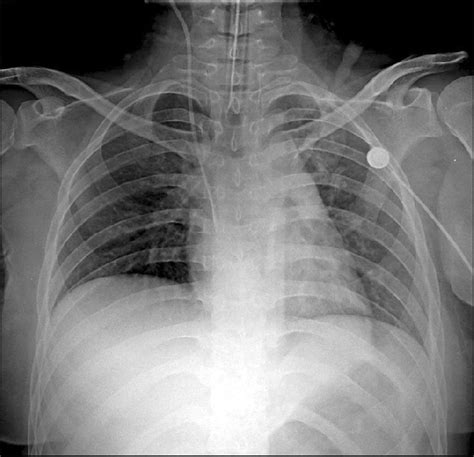

Now, let’s talk about how X-rays help us diagnose pulmonary interstitial edema . Chest X-rays are like the workhorses of medical imaging, especially when it comes to lung issues. They use a small dose of radiation to create pictures of the structures inside your chest, including your lungs, heart, and bones. When a radiologist or doctor looks at a chest X-ray, they’re looking for specific patterns that indicate fluid buildup in the interstitial space. One of the classic signs they look for is something called “Kerley B lines.” These are tiny, short, horizontal lines that appear at the lung periphery, usually near the costophrenic angles (where your ribs meet your diaphragm). They represent fluid in the interlobular septa, which are the small walls that divide the lung tissue. Another key indicator is the thickening of the interlobar fissures, which are the lines that separate different lobes of the lung. You might also see a general increase in lung markings or a haziness that suggests fluid is present. The heart size might also be important to note on an X-ray; an enlarged heart can often be a clue that heart failure is the underlying cause of the edema. Sometimes, the X-ray might show fluid accumulating in the pleural space as well (pleural effusion), which is another sign of fluid overload. The beauty of the X-ray is that it’s quick, widely available, and relatively inexpensive. It gives doctors a good initial look at what’s going on inside the chest and can help them decide if further tests are needed. It’s not always definitive on its own, especially in the very early stages, but it’s an invaluable first step in narrowing down the possibilities and guiding subsequent management. Think of it as the first alert system, flagging potential trouble that needs a closer look. The interpretation requires a skilled eye, as subtle changes can sometimes be missed or misinterpreted, but its overall contribution to diagnosing conditions like pulmonary interstitial edema is undeniable. It provides a visual map of the lung’s condition, allowing medical professionals to see beyond the symptoms and get to the root of the problem.

Alright guys, let’s get into the nitty-gritty of what doctors actually see on a pulmonary interstitial edema x-ray . When we talk about visualizing these signs, we’re essentially looking for indirect evidence of that excess fluid in the lung tissue. As I mentioned, Kerley B lines are a big one. Picture them as really fine, pencil-thin lines, usually a centimeter or two long, running perpendicular to the pleura (the outer lining of the lungs). They’re essentially the thickened walls of the tiny lung lobules due to fluid. They’re often found at the lung bases because fluid tends to settle lower down due to gravity. Another sign is the thickening of the interlobar fissures . These are the fissures that divide the lobes of the lung. Normally, they’re barely visible on an X-ray, but with interstitial edema, the fluid accumulation around them can make them appear more prominent and distinct, almost like sharp, dark lines. You might also notice a generalized increase in bronchovascular markings . These are the lines representing the airways (bronchi) and blood vessels within the lungs. When fluid accumulates in the interstitial space surrounding them, these markings can look more prominent, smudged, or “dirty.” It’s like seeing the trees through a slightly foggy window – the general pattern is there, but it’s less crisp. Sometimes, especially if the edema is more severe or starting to involve the air sacs, you might see what’s called “bat wing” or “butterfly” distribution of haziness or opacities, primarily around the center of the lungs. This pattern is more typical of alveolar edema but can be seen in more advanced interstitial edema too. We also look at the heart size . A significantly enlarged heart on an X-ray is a strong indicator of underlying heart disease, a common cause of pulmonary edema. The pleura itself might show thickening, and you could see blunting of the costophrenic angles if there’s a pleural effusion, which is fluid in the space between the lungs and the chest wall. So, essentially, the radiologist is piecing together these subtle clues – the fine lines, the thickened borders, the hazy patterns, and the heart’s appearance – to build a picture of what’s happening within the lungs. It’s a bit like being a detective, looking for the tell-tale signs of fluid overload that aren’t directly visible but leave their imprint on the X-ray image. The clarity and angle of the X-ray (PA and lateral views are standard) are crucial for spotting these subtle changes effectively. Sometimes, comparison with previous X-rays can be really helpful to see if these changes are new or have progressed.